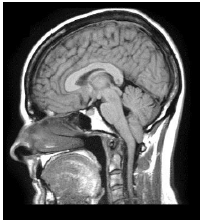

A ressonância magnética de crânio apresenta uma malformação, muitas vezes congênita, capaz de causar sintomas neurológicos como dor cervical; vertigem; perda de equilíbrio; e, disfagia.

Podemos afirmar que tal condição se refere à síndrome de: